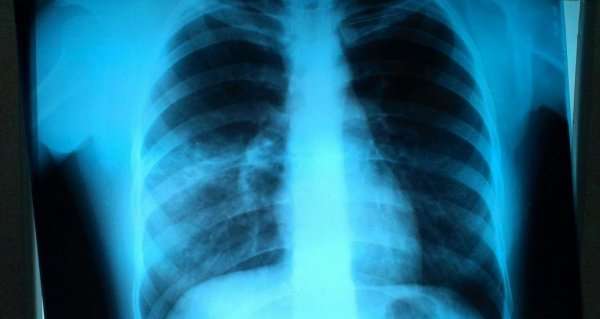

Рентгенография – один из основных и обязательных методов исследования, проведение которого необходимо при подозрении на пневмонию. Посредством рентгена подтверждается или исключается диагноз. Только так врач может увидеть полную картину развития заболевания и сделать необходимое заключение.

Расшифровать данные рентгеновского снимка способен только опытный рентгенолог. Также необходимо знать, что основным рентгенологическим признаком воспаления легких является участок или участки затемнения легочного поля. Однако, здоровые легкие на снимке имеют темный цвет, в то время как затемнения являются белыми участками.

Теперь рассмотрим различные виды пневмонии на фото рентгеновских снимков.